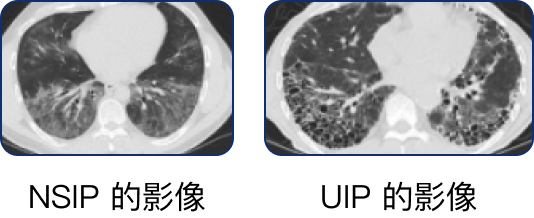

高解析電腦斷層掃描 (HRCT)3

自體免疫疾病相關的肺纖維化病人 HRCT 檢查結果中,最常出現非特異性間質性肺病 (NSIP) 及尋常性間質性肺病 (UIP) 的影像,較少出現器質性肺炎 (OP) 的影像。

• 硬皮症病人的影像結果較常出現 NSIP,而 UIP 則可見於 40% 的硬皮症病人。

• 多發性肌炎及皮肌炎病人的影像結果較常出現 NSIP 與 OP 的重疊影像。